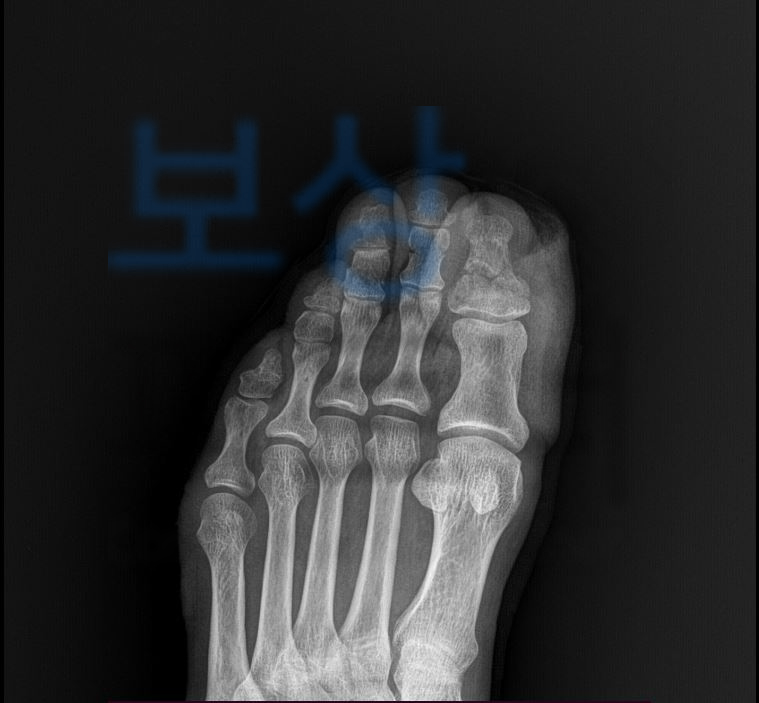

작업중 합판이 발가락 위로

떨어지는 재해를 당하셨습니다.

엄지발가락 골절부터

가운데발가락의 골절로 핀 고정술을 받으셔야 했습니다. 먼저 일하다 다친 사고이기에 의무보험인 산재보험에서 보상받을 수 있습니다. 의뢰인은 원무과의 도움으로 산재 최소 신청을 무사히 진행하셔서 요양급여 및 휴업급여를 지급받고 계셨는데요,